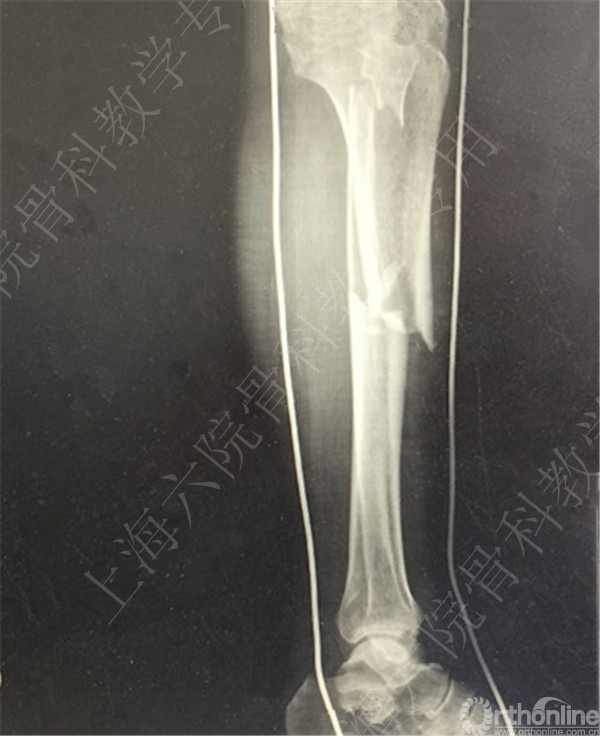

患者车祸伤至左胫腓骨开发性骨折,急诊予清除缝合+外固定术。

待软组织条件好转后,择期行右胫腓骨外固定拆除术+切开复位内固定术。

术后X线摄片示:骨折对位对线欠佳,稍成角。

患者复查,X线摄片示:骨折对位对线差,左胫骨立线欠佳,成角。